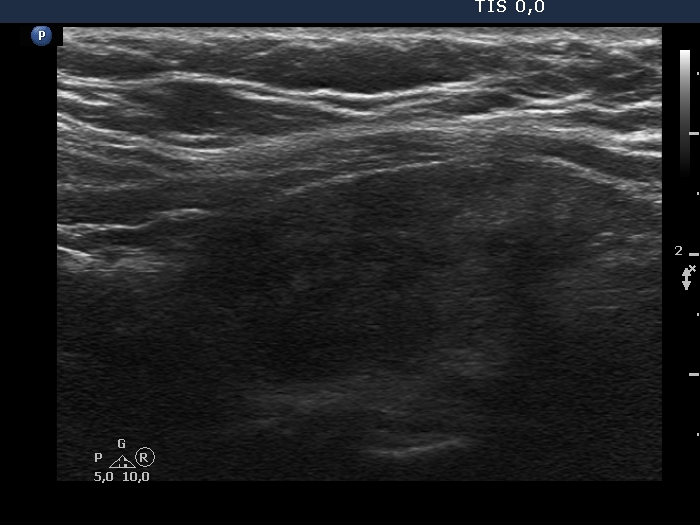

Lymphocytic thyroiditis - case 1442

Follow-up investigation 5 years after the first visit (ultrasonographic picture 5)

Left lobe, longitudinal scan.